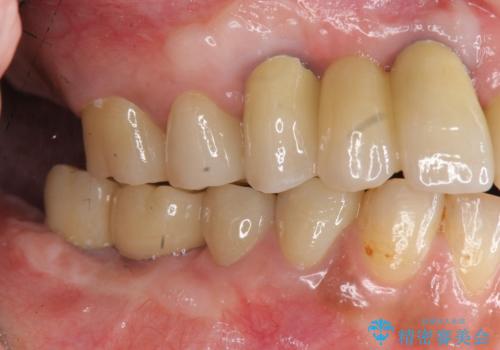

痛くて噛めない インプラントで全て治療したい

- 痛くて噛めない、これまでだましだまし治療をしてきたがこれを機にすべてきっちりと治したい、口の中の悩みを解決したいと来院されました。

抜歯や歯周病治療、欠損補綴を含め、全顎的な治療を計画・提案します。